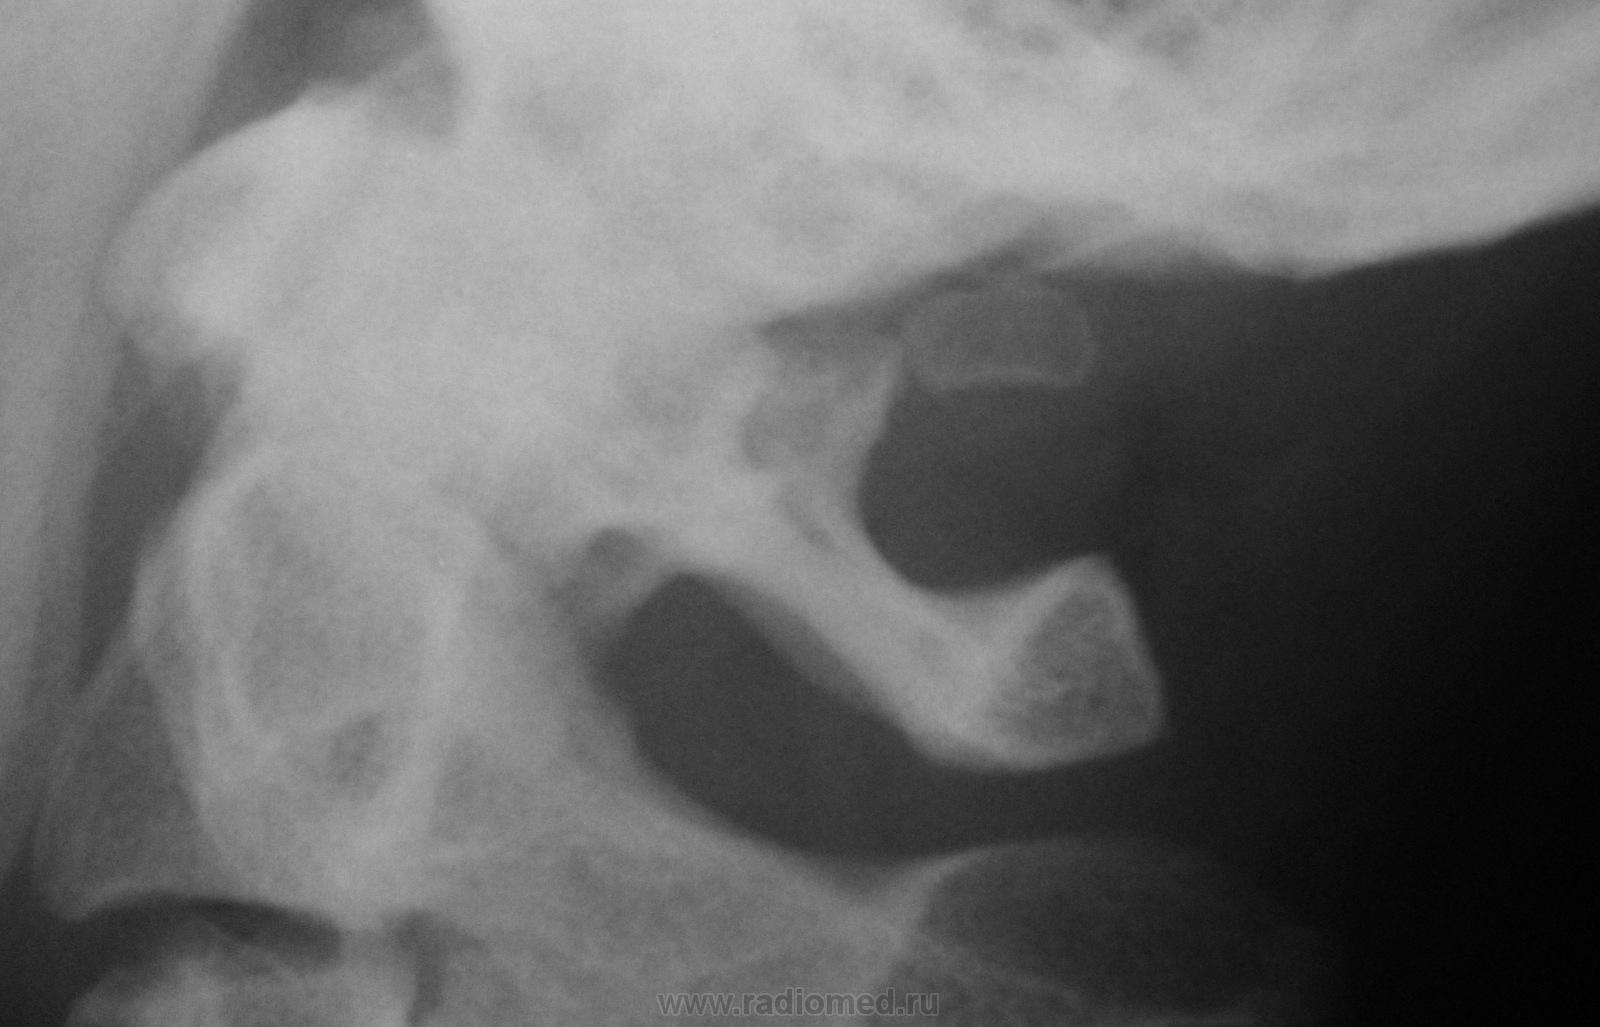

Уважаемые коллеги! Сколько лет ни работай, а попадаются невиданные ранее картинки. Жду вашего мнения, что за костный фрагмент над задней дугой С1? Вариант сесамовидной косточки, разновидность аномалии Киммерли или перелом при аномалии Киммерли? Известно, что подростку упала штанга как раз в область основания затылочной кости. Лично я склоняюсь к добавочной косточке, т.к. контуры её четкие, с замыкательной пластинкой вокруг. Травматологи тоже в сомнениях.....

склоняюсь к добавочной косточке, т.к. контуры её четкие, с замыкательной пластинкой вокруг.

+1.По типу свобоного заднего проатланта ("Дифференциальная рентгенодиагностика заболеваний позвоночника" М.К. Михайлов, Г.И.Володина,Е.К. Ларюкова страница 8.Рисунок №7).

Благодарю за картинку. Только на ней проатлант представлен очень мелкой косточкой, а здесь вполне приличные размеры. Возможно, что бывают и такие варианты. Хорошо, что травматологи гипс не наложили:)))

Согласен с Almo. И этих проатлантов достаточно много. Названия их от места расположения: задний ,передний, боковой и т.д. У товарища Орлова "Рентгенодиагностика позвоночника для мануальных терапевтов", тоже они описаны.

+1 к скободному заднему проатланту